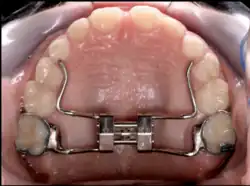

Rapid palatal expansion

Rapid palatal expansion (RPE) or Rapid Maxillary Expansion (RME) is an expansion technique where expansion of 0.5 mm to 1 mm is achieved each day until the posterior crossbite is relieved. The expander works by turning a key inside the center of the expander. The turn of this key will push the arms of the expander.

For stability purposes, the RPE usually remain in the patient's mouth anywhere between 3–6 months, but this time may vary between patients. This is often known as "six month retention period" during which the bone fills the gap in the maxilla that was created by the expansion process. To prevent any type of relapse, a retainer is given to the patient to keep the teeth in proper alignment.[6] RPE can be tooth supported, bone supported or both.